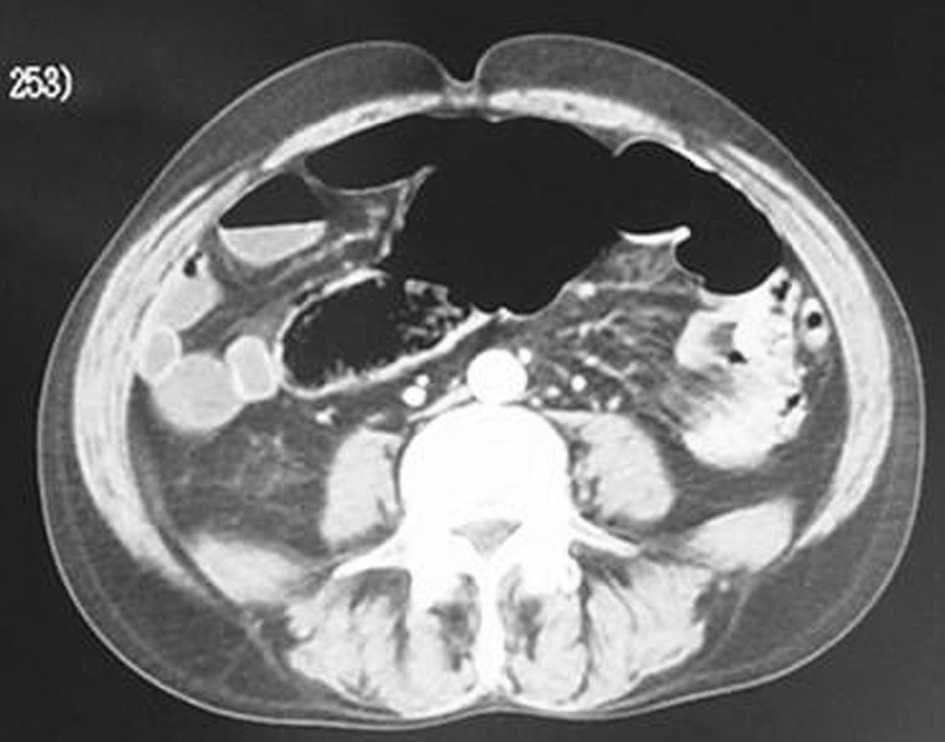

En la radiografía de abdomen se observó una burbuja aérea con dilatación de las asas de delgado, sin neumoperitoneo. La tomografía computarizada (fig. 1) apuntó la sospecha diagnóstica de vólvulo de colon y se indicó enema opaco (fig. 2), que puso de manifiesto un vólvulo cecal, por lo que se procedió a realizar una intervención quirúrgica.

Fig. 1.